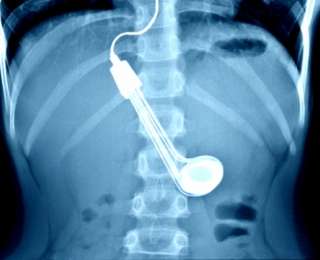

Красноярским врачам пришлось бороться за жизнь молодого человека, который умудрился проглотить кипятильник. Бытовой прибор застрял у него в пищеводе.

Как сообщают "Вести", медики успешно справились с задачей - они спасли пациента от удушья и извлекли кипятильник, не повредив внутренних органов.

"С учетом того, что диаметр пищевода в спокойном состоянии - 2-3 см, а кипятильник растянул его в 4-5 раз, манипуляция по удалению инородного тела предстояла трудная", - рассказали врачи.

Зачем молодой человек решил проглотить кипятильник, не ясно. Сам он утверждает, что сделал это случайно.